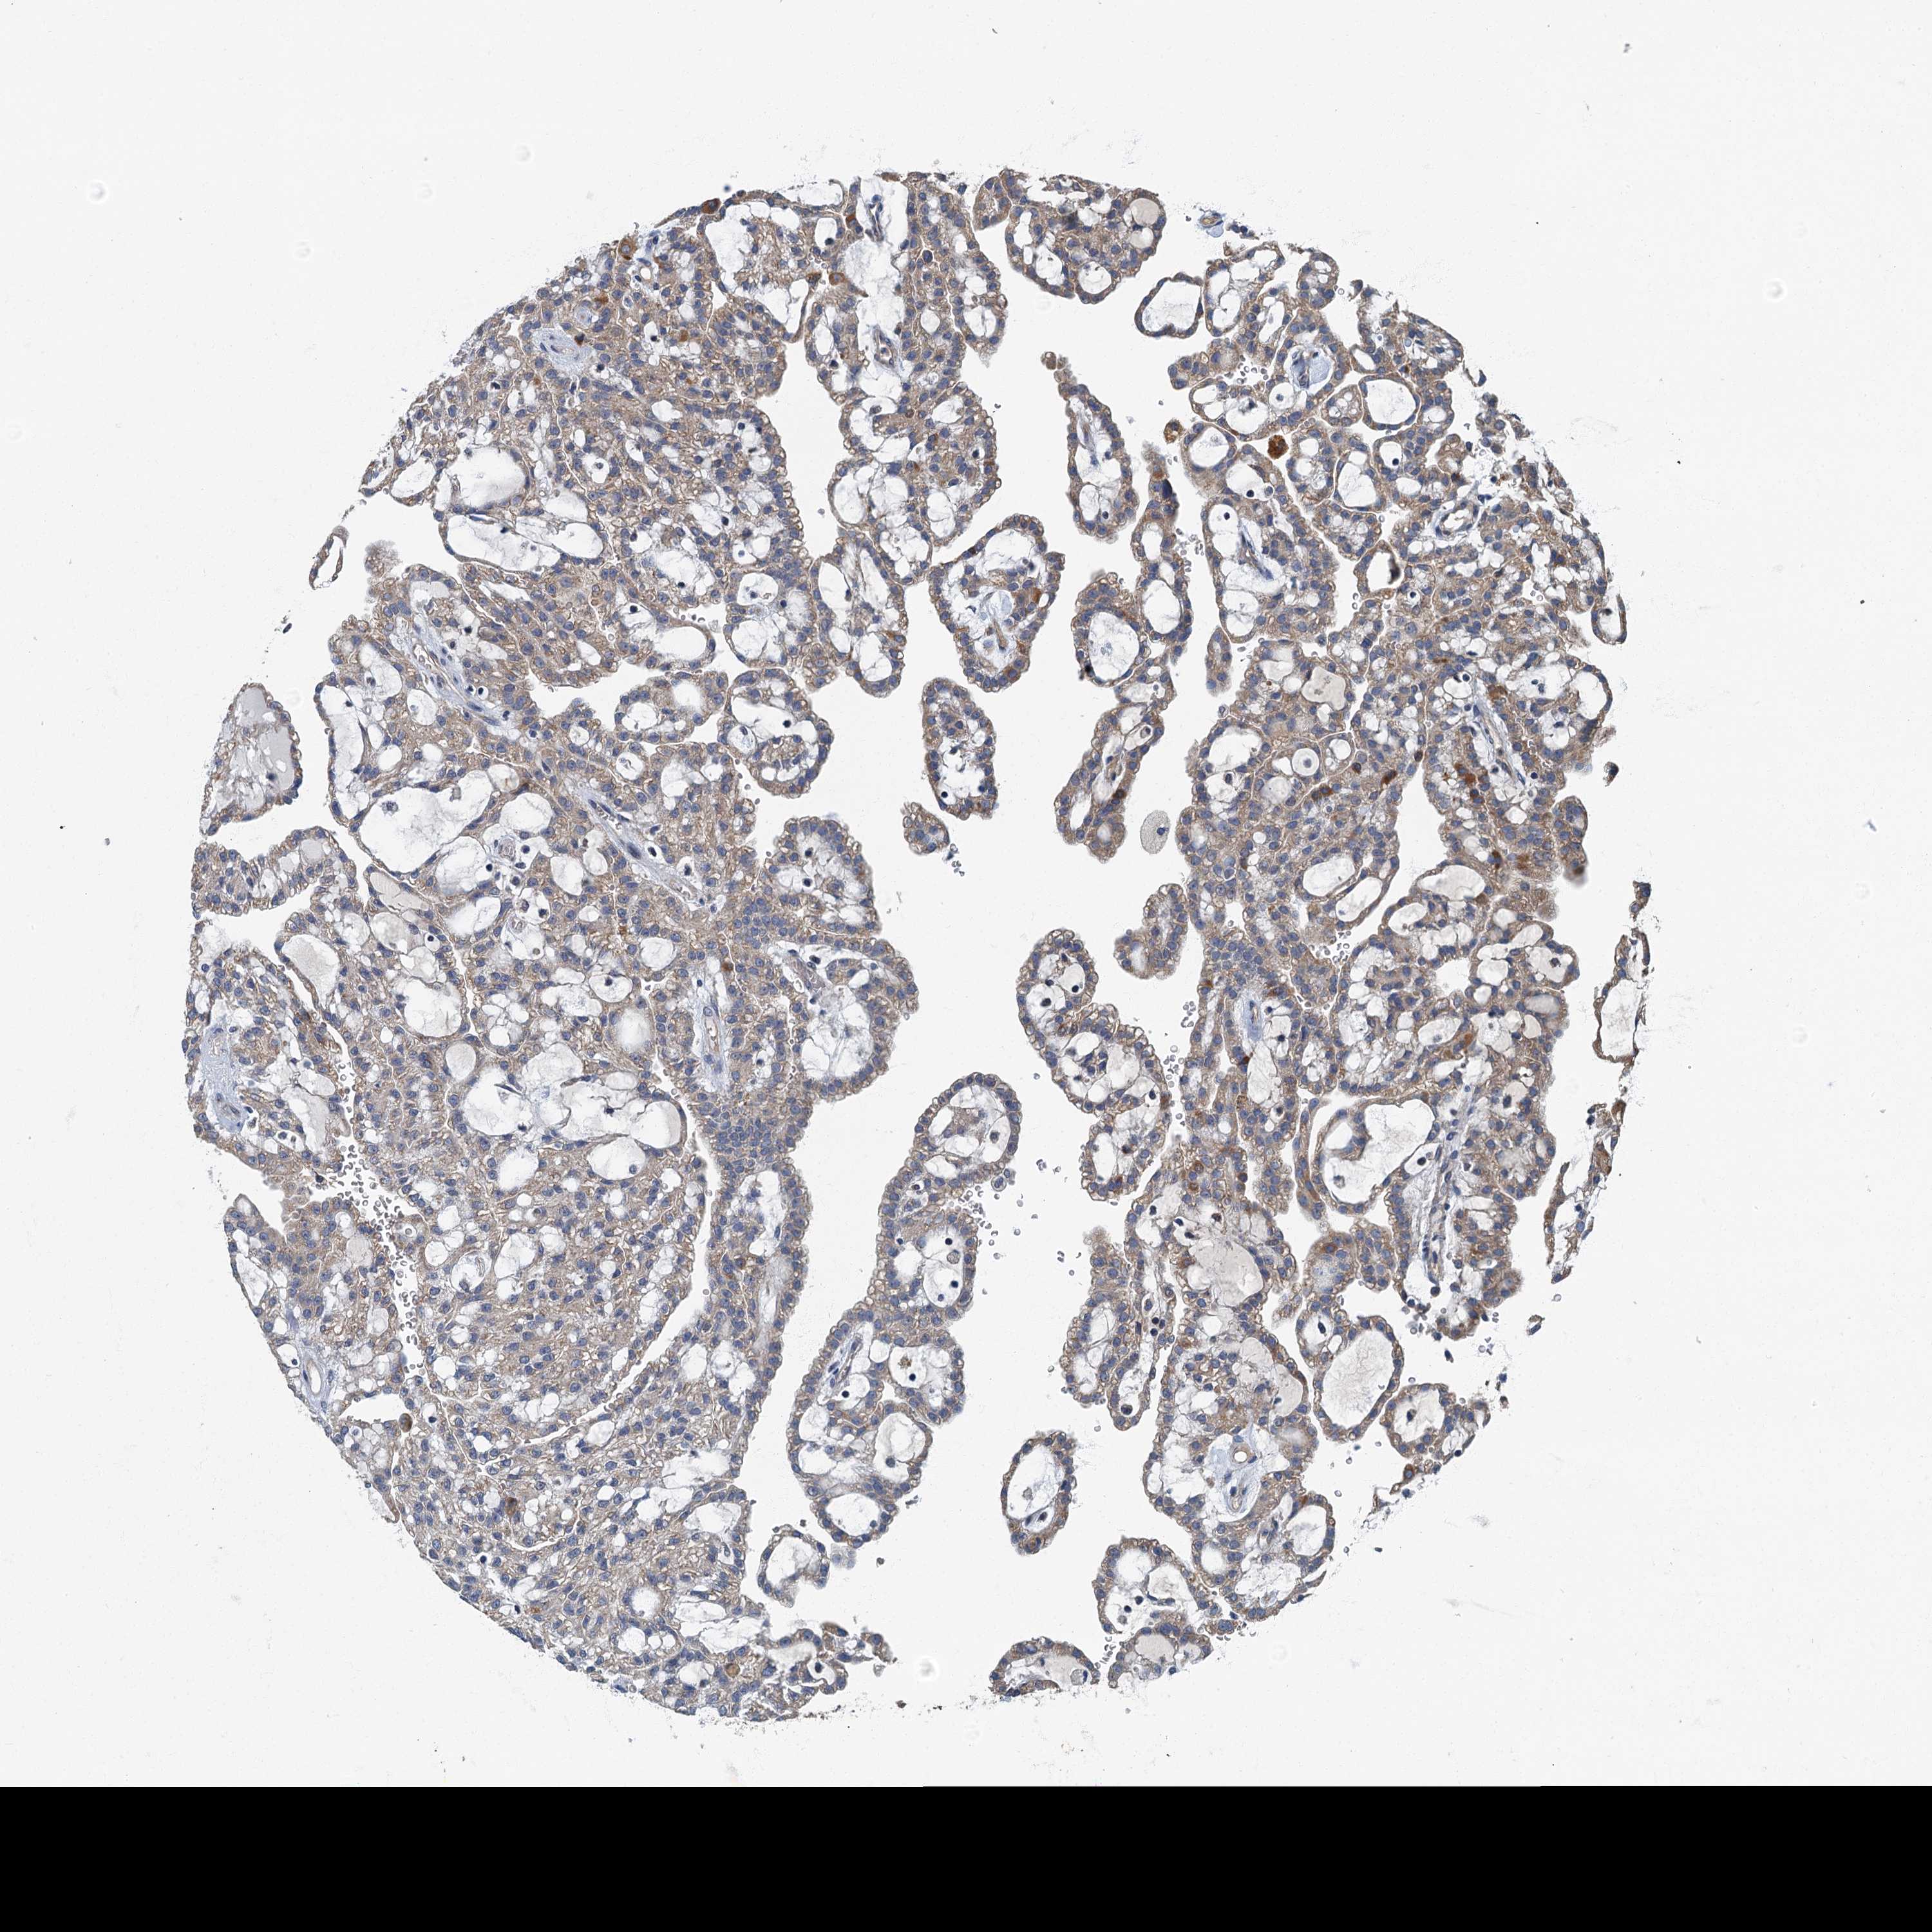

KIDNEY RENAL PAPILLARY CELL CARCINOMA (TCGA) - Interactive survival scatter ploti

The Survival Scatter plot shows the clinical status (i.e. dead or alive) for all individuals in the patient cohort, based on the same data that underlies the corresponding Kaplan-Meier plots. Patients that are alive at last time for follow-up are shown in blue and patients who have died during the study are shown in red.

The x-axis shows the expression levels (FPKM) of the investigated gene in the tumor tissue at the time of diagnosis. The y-axis shows the follow-up time after diagnosis (years). Both axes are complimented with kernel density curves demonstrating the data density over the axes. The top density plot shows the expression levels (FPKM) distribution among dead (red) and alive patients (blue). The right density plot shows the data density of the survived years of dead patients with high and low expression levels respectively, stratified using the cutoff indicated by the vertical dashed line through the Survival Scatter plot. This cutoff is automatically defined based on the FPKM cutoff that minimizes the p-score. The cutoff can be changed by dragging the vertical line or by entering a cutoff value in the square labeled "Current cut-off".

Under the Survival Scatter plot the p-score landscape (black curve; left axis) is shown together with dead median separation (red curve; right axis). Dead median separation is the difference in median mRNA expression between patients who have died with high and low expression, respectively. It is calculated as follows: median FPKM expression of dead patients with high expression - median FPKM expression of dead patients with low expression. This is intended to aid the user in visually exploring custom cutoffs and the associated p-scores and dead median separation.

Individual patient data is displayed and can be filtered by clicking on one or more of the category buttons on the top of the page. Categories describing expression level and patient information include: high, low, alive, dead, female, male and tumor stages. The scale of the x-axis can be toggled between linear and log-scale by clicking on the "x log" button. Mouse-over function shows TCGA ID, patient information and mRNA expression (FPKM) for each patient.

& Survival analysisi

Kaplan-Meier plots summarize results from analysis of correlation between mRNA expression level and patient survival. Patients were divided based on level of expression into one of the two groups "low" (under cut off) or "high" (over cut off). X-axis shows time for survival (years) and y-axis shows the probability of survival, where 1.0 corresponds to 100 percent.

DDX49 is not prognostic in Kidney Renal Papillary Cell Carcinoma (TCGA)

Best expression cut offi